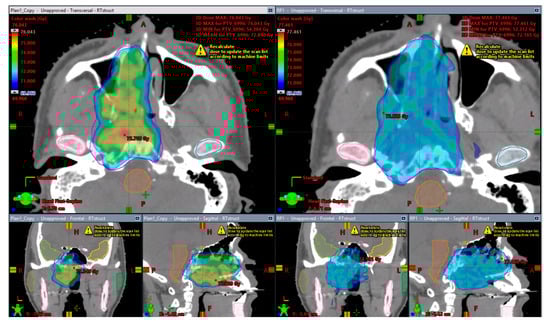

3.2. NRG-BN001 Proton Plan Quality Review

3.3. NRG-HN001 Proton Plan Quality Review